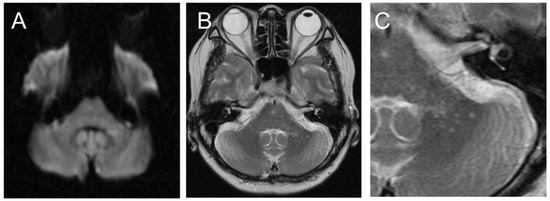

Akimoto, T.; Hara, M.; Hirose, S.; Nakamichi, K.; Nakajima, H. Cerebellar Progressive Multifocal Leukoencephalopathy Mimicking Anti-Yo-Antibody-Associated Rapidly Progressive Cerebellar Syndrome. Neurol. Int. 2023, 15, 917-925. https://doi.org/10.3390/neurolint15030059